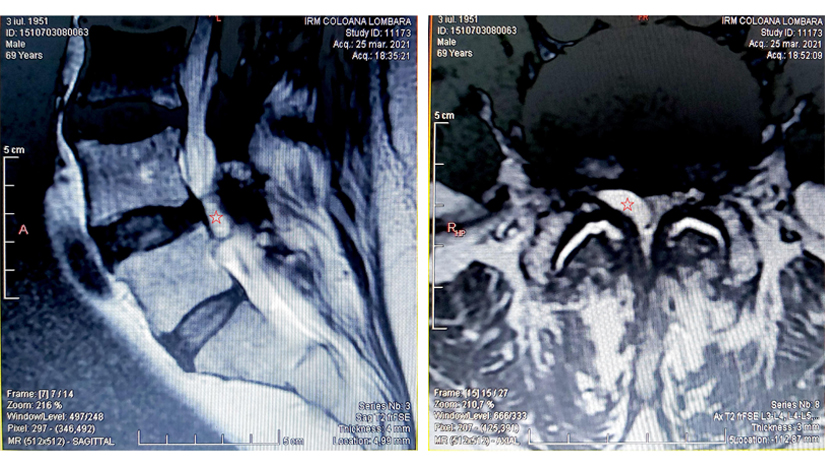

Chistul sinovial lombar ocupa aproape intregul canal vertebral lombar L4L5

Pacientul efectuase deja o investigatie RMN de coloana lombara intr-un alt centru si rezultatul era elocvent: la inaltimea discului intervertebral L4L5, aproape toata suprafata de sectiune a canalului vertebral lombar, prin care in mod normal coboara radacinile nervilor lombo-sacrati inconjurate de LCR si grasime epidurala, era ocupata de un chist (marcat cu steluta rosie) aparent conectat cu articulatia fatetara L4L5 dreapta.

In plus, si articulatia fatetara de pe stanga daduse nastere altui chist mai mic, situat in afara canalului, in muschii paravertebrali, deci inofensiv. In schimb, chistul L4L5 ocupa aproape tot spatiul de trecere disponibil pentru nervii care dirijau sensibilitatea si miscarile ambelor membre inferioare de la genunchi in jos, precum si functionarea vezicii urinare, a capatului inferior al tubului digestiv si a organelor genitale.